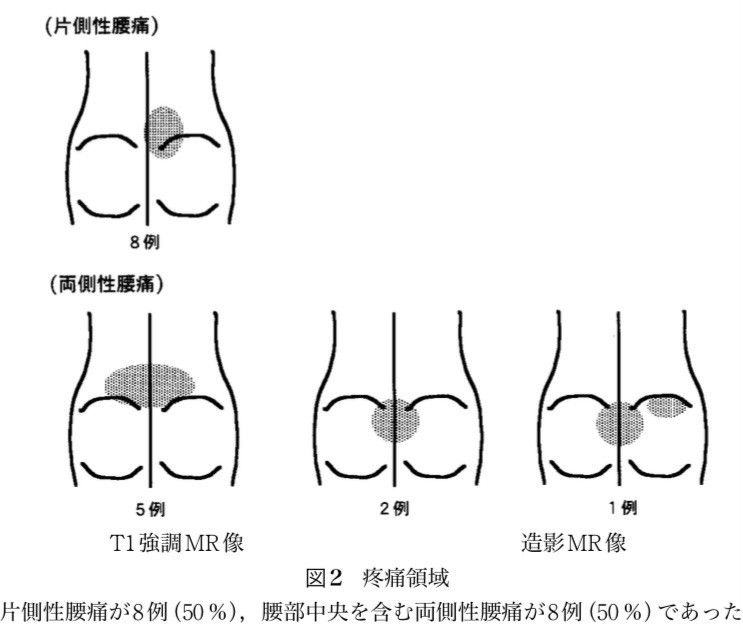

矢印のところが椎間板が痛んで炎症し痛みを引き起こしている場所です。

以前は両側性の痛みが多いと言われていましたが、この論文からだと片側も50%は認められたということです。 痛みは動けなくなるくらい痛みや 前かがみをすることで痛いことが多いです。

炎症期はそらしても痛いです。 発生するきっかけは ・何気ない動作 ・ものを取るときに前かがみになった ・中腰での動作 ・重いものを持ち上げる 特に何気ない動作が一番多いです。 治療は炎症由来なのでロキソニン内服とコルセットをして安静にすればすぐに痛みが落ち着きます。

椎間板の痛みなので腰の筋肉をマッサージしても改善はしません。 炎症が落ち着けば痛みはほぼ落ち着き時間と共に改善します。